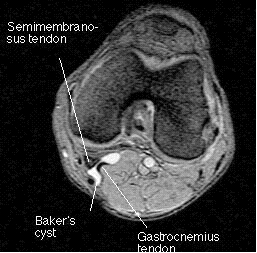

标题: MRI0032:45岁膝痛结果 [打印本页]

其他的英文都明白,就一个需要老师解释:semimembranosus什么意思?抱歉!!我英文太差。象是哪块肌肉?

半膜肌【肌腱】